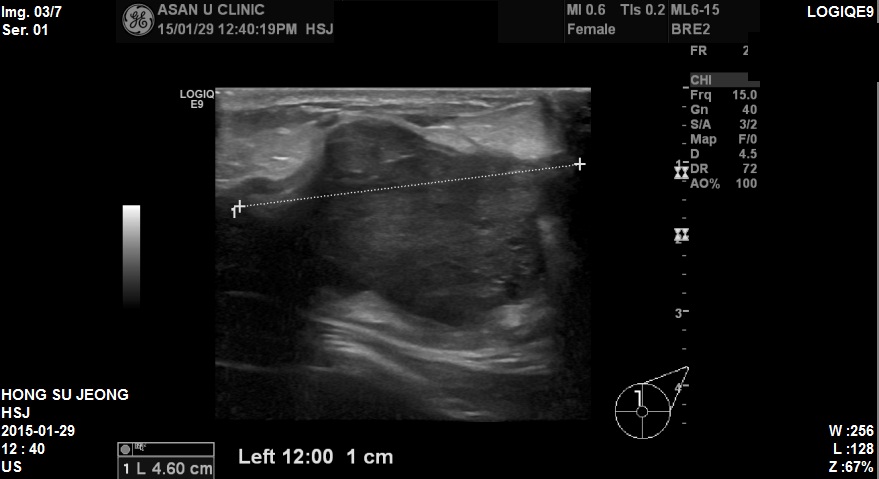

건진이상소견으로 내원하신 48세여자분이십니다.

본원 초음파 검사상 좌측유방에 4cm 가 넘는 혹이 발견되었고,

조직검사결과 침윤성 유관암 진단되었습니다.